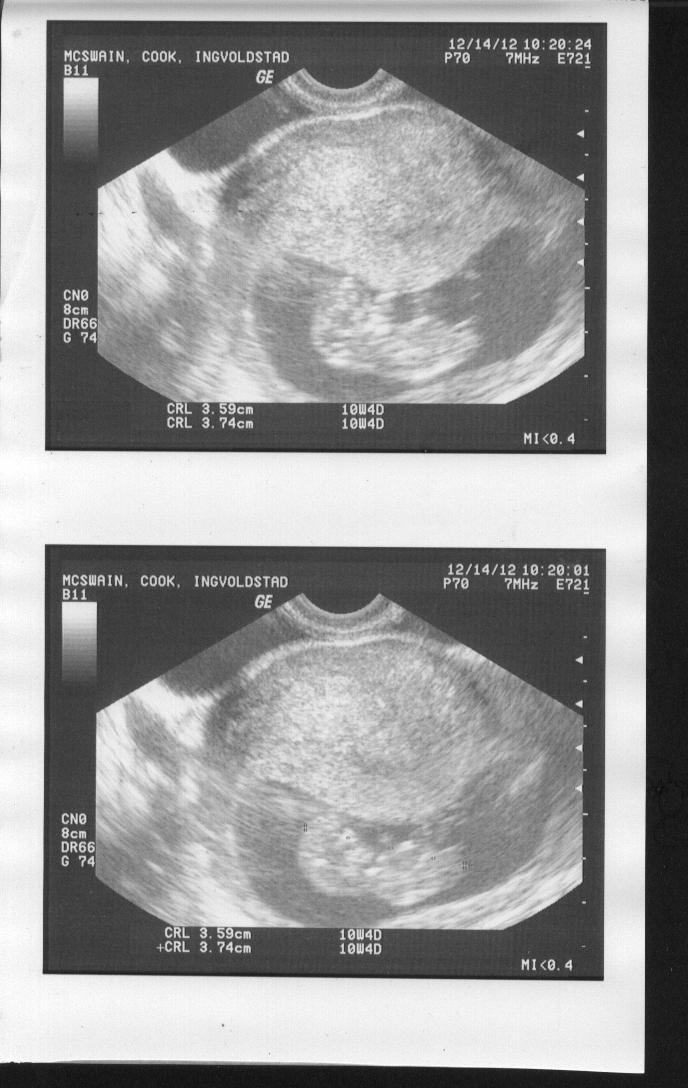

Hey there! I know it's super early, but would love to hear your guesses. I am so excited to find out what this baby is!

UPDATE! It's a... (11 Week U/S...Early, But Would Love Guesses!)

Ack! All these boy guesses! I know it's early, but it looks so different from my 2nd son's 12 wk u/s (where the nub was classic boy). This one just looks more flat to me, but I'm still learning about all of this!

Totally 50/50 as most start out relatively flat (like your baby's) and then angle up over the course of the 11th week.